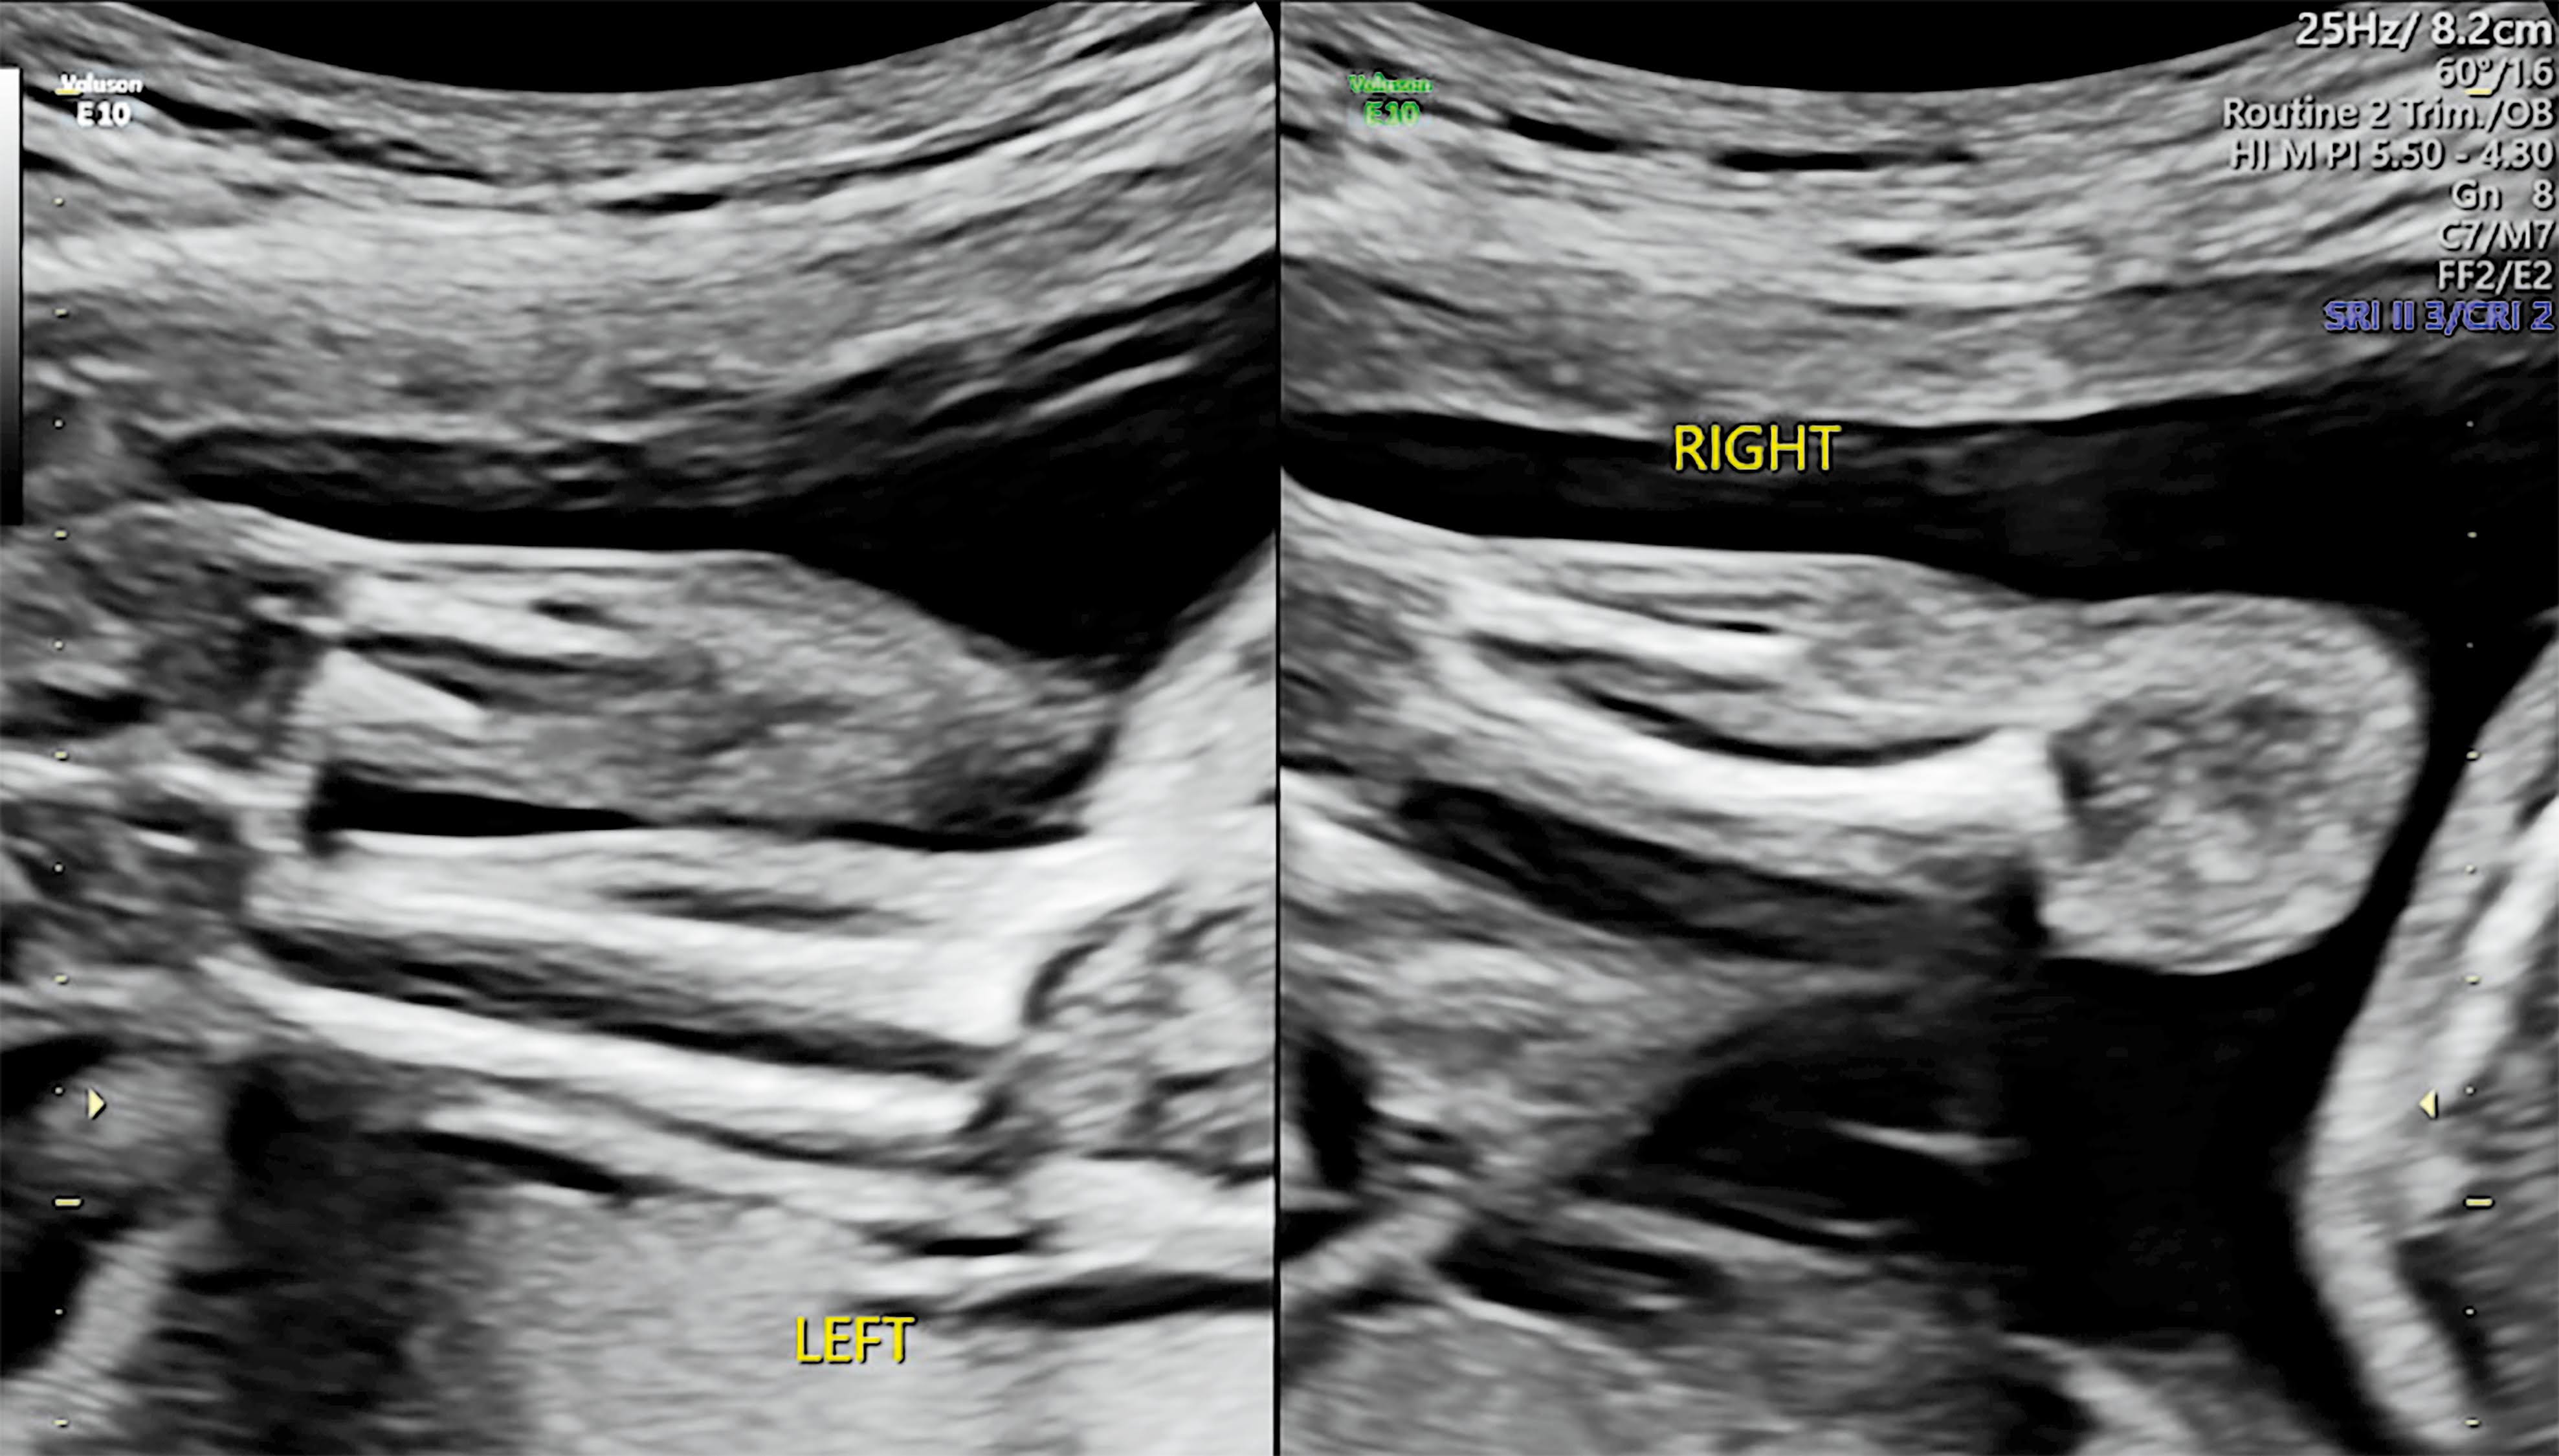

| (圖一)左側影像上可見右側腓骨部分缺失(黃色箭號),右側影像為左側下肢骨頭正常外觀 |

此個案在來診之前已經執行過羊膜穿刺染色體核型的檢查,於妊娠22週時來診執行中期結構篩檢,在檢查過程中發現胎兒的右側腓骨半肢畸形(圖一),在測量各個長骨數值後,右側腓骨長度數值明顯落於此週數的低標以下,右側脛骨長度數值雖然落於正常範圍但稍短於左側,其他結構發現還有右腳第四趾curly toe(圖二),但在超音波下並沒有發現合併其他足部及踝關節相關異常。

| (圖四)個案於23週時的超音波影像,明顯可見右側腓骨近端缺失外觀 |